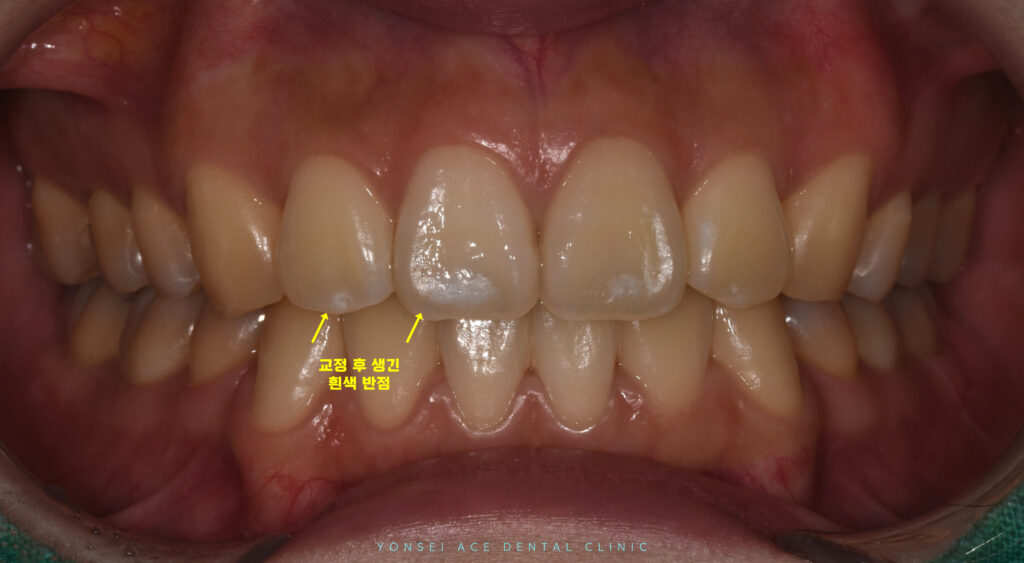

위 환자분께서는

교정 치료 중 생긴 앞니의 흰 반점이

웃거나 말할 때 마다 보이는게 싫으시다며

본원에 내원해 주셨는데요.

현재는 교정 치료가

완료된 상태였습니다.

교정을 진행하면서 브라켓이 붙어 있었을 때는

장치에 가려져 잘 인지하지 못했던 부분이

브라켓이 제거되면서 선명하게 드러났습니다.

충치로 진행된 단계는 아니었지만

심미적으로 부담을 느끼실 수 있는 위치였는데요.